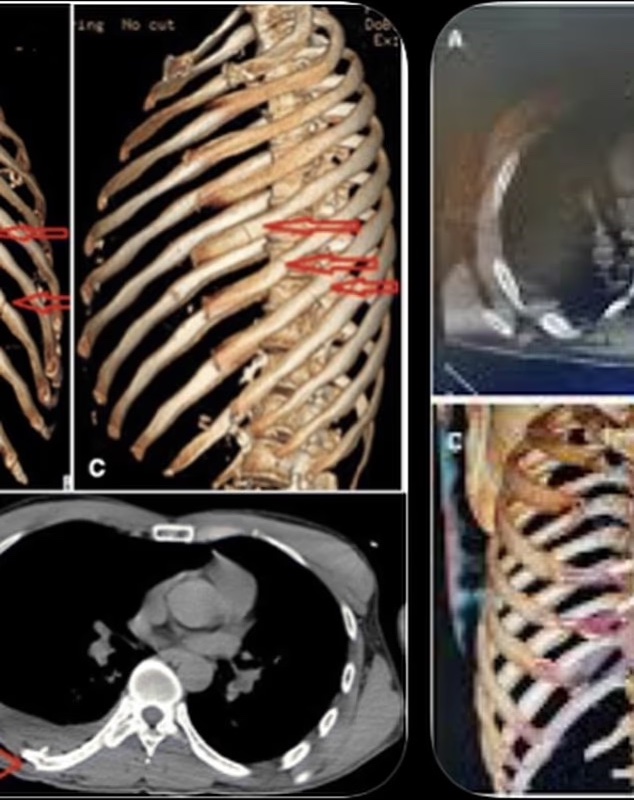

Friends, fans, and followers first learned about the incident on January 26, 2026, when Corey posted photos from his hospital bed on Instagram. In the images, his face was visibly bruised and scraped, and X-rays showed the extent of the rib damage. He captioned the post with an honest and straightforward note to fans: “Pretty messed up, but I’m good. Crash bars are awesome. 3 nights in the hospital, 11 breaks in my rib cage.”